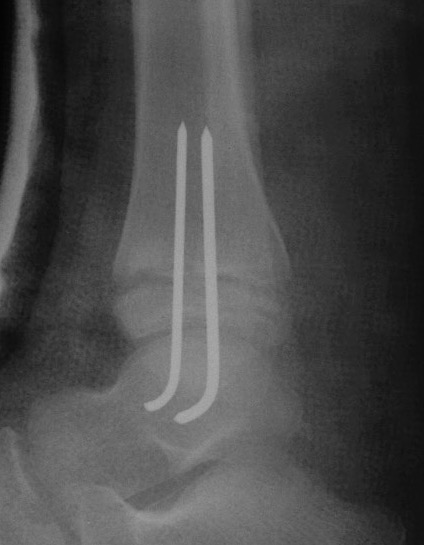

Xray

Type III / Tillaux on AP

Type II on lateral

CT

Type III on coronal

Type II on sagittal

3 point star on axial

Management

ORIF

- > 2mm displacement

- usually anterolateral approach to reduce

- epiphyseal medial-lateral screw

- metaphyseal AP screw